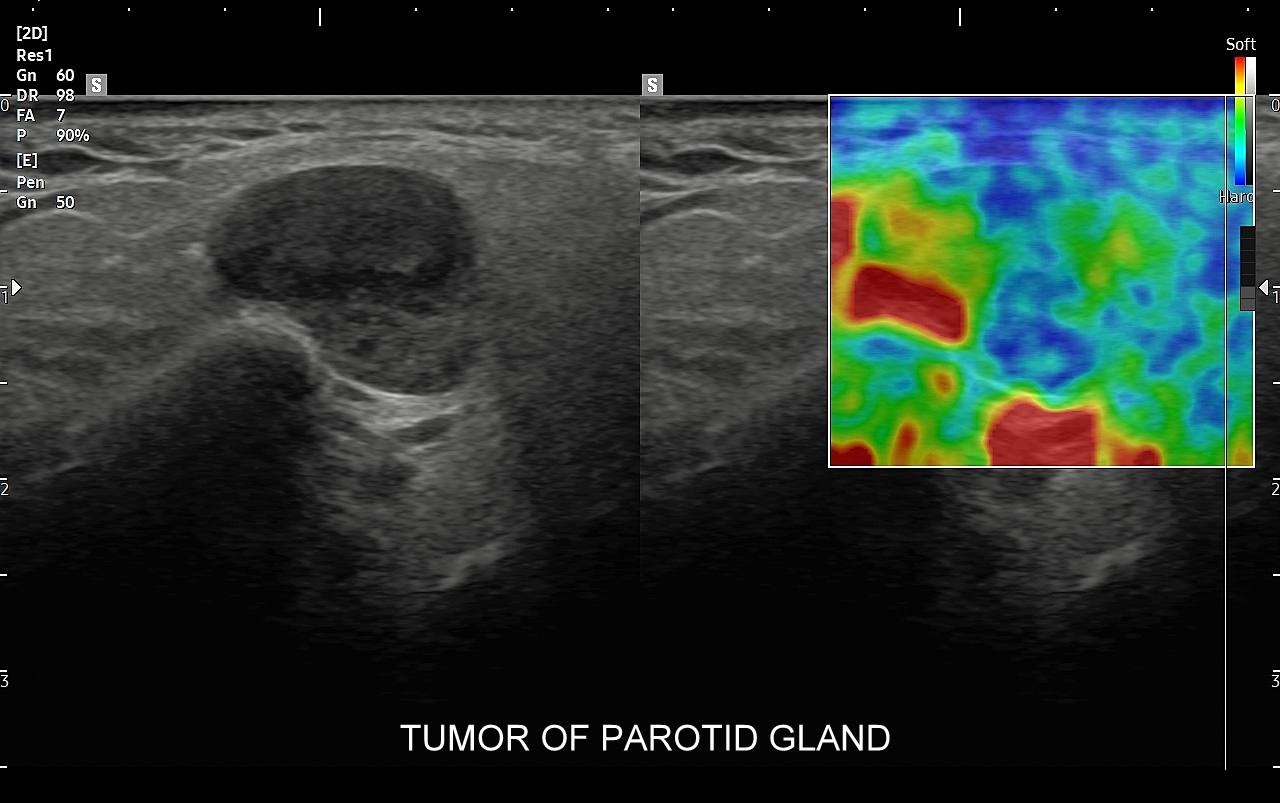

Przykładami guzów nienowotworowych w śliniankach są odczynowe węzły chłonne i torbiele. Najczęstszymi nowotworami łagodnymi są gruczolak wielopostaciowy, zwany także guzem mieszanym (tzw. tumor mixtus) oraz gruczolak limfatyczny (tzw. guz Warthina) posiadający sonograficzne cechy nowotworu lito-torbielowatego. Guz mieszany jest zmianą wolno rosnącą z tendencją do miejscowej wznowy po zabiegu chirurgicznej resekcji. Z kolei guz limfatyczny, czyli guz Warthina, częściej występuje u palaczy papierosów, może być obustronny, a ze względu na swój histologiczny charakter może pojawić się po przebyciu infekcji górnych dróg oddechowych. Wśród nowotworów złośliwych dominują rak śluzowo-naskórkowy, gruczołowo-torbielowaty i gruczolakorak. Nowotwory ślinianek najczęściej umiejscawiają się w śliniance przyusznej, a większość z nich ma charakter łagodny. W przypadku nowotworów lokalizujących się w pozostałych śliniankach częściej spotyka się guzy złośliwe.

Pacjenci ze skierowaniem na badanie USG ślinianek zgłaszają się do Pracowni zwykle w przypadku dolegliwości subiektywnych bądź obiektywnych zlokalizowanych w okolicy żuchwy i górnych partii szyi. Należy jednakże mieć na uwadze, że patologie umiejscowione w wymienionych obszarach nie zawsze odpowiadają chorobom ślinianek, a mogą dotyczyć np. węzłów chłonnych, migdałków, czy innych tkanek miękkich szyi. USG to podstawowe badanie obrazowe ślinianek. Jest procedurą bezpieczną i dokładną, a w Pracowni dr Szczepańskiego ślinianki oceniane są nowoczesną metodą MPUS (multiparametryczne USG) z zastosowaniem trybów mikrounaczynienia i elastografii. W przypadku konieczności oceny głębokich części ślinianek przyusznych albo zaplanowania operacji w obrębie szyi wykonuje się tomografię komputerową lub rezonans magnetyczny szyi.